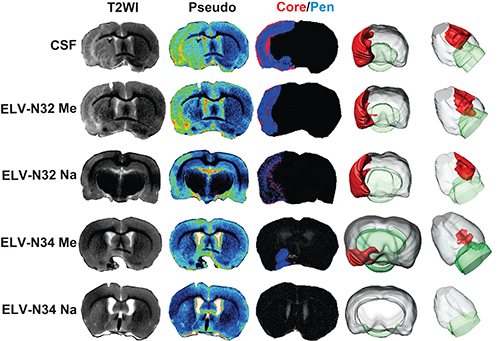

LSU Health New Orleans Discovery May Complement Recovery from Ischemic Stroke

A study led by Nicolas Bazan, MD, PhD, Director of the LSU Health New Orleans Neuroscience Center, pinpointed which cells within specific areas of the brain are involved in post-stroke response and found that the delivery of precursors of Elovanoids, a class of molecules that synchronize cell-to-cell communication and neuroinflammation/immune activity in response to injury, improved neurological deficit in an experimental model of ischemic stroke. More

LSU Health New Orleans Researchers Discover Potential New Rx Strategy for Ischemic Stroke

A study conducted by scientists at LSU Health New Orleans’ Neuroscience Center of Excellence reports that the additive neuroprotection of a combination of two omega-3 fatty acid-derived signaling molecules is more effective in protecting brain cells and increasing recovery from stroke in an experimental model than a single drug. More